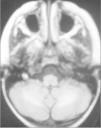

Caso 2La paciente es una niña de 6 años diagnosticada de LLA de riesgo normal. Se inicia tratamiento con vincristina, daunorrubicina, corticoides, dosis altas de metotrexato, asparraginasa, citarabina, mercaptopurina y triple terapia intratecal. Se alcanza la remisión completa con normalidad morfológica, de inmunofenotipo, citogenética y enfermedad residual menor del 0,1 %. Tras la primera reinducción de la fase de mantenimiento con vincristina, ciclofosfamida y corticoides se observa una aplasia grave con decaimiento, febrícula, vómitos, íleo paralítico, crisis convulsivas focales e hipertensión arterial (HTA) con cifras de 150/100 mmHg. Ingresa en la unidad de cuidados intensivos, se suspende la quimioterapia y se instaura tratamiento de soporte y sintomático. Se realiza estudio del líquido cefalorraquídeo (LCR) y médula ósea, así como tomografía computarizada (TC) craneal y electroencefalograma (EEG), que son normales. En la RM craneal se observa en la secuencia FLAIR T2 un aumento de señal en la zona subcortical de varios surcos de la zona medial occipital izquierda (fig. 4).

La evolución a los 7 días fue favorable, con normalización de la sintomatología neurológica, y el estudio de RM a las 4 semanas fue normal.

Ante la sospecha de LEPR, se deben realizar pruebas de imagen, en especial, RM ya que es la técnica radiológica más sensible para la demostración del edema cerebral y puede evidenciar lesiones pequeñas y focales no demostradas con la tomografía. Suele observarse alteraciones de la sustancia blanca supratentorial e infratentorial de límites poco definidos consecuencia del edema cerebral. También puede verse afectación cortical con borrado de surcos y alteraciones en otras zonas, como la afectación cerebelosa de nuestra primera paciente. La RM mostraría en secuencias T1 una señal hipointensa, y en T2, FLAIR y densidad protónica, hiperintensa. Deben incluirse imágenes de difusión de la RM, interesantes desde el punto de vista diagnóstico, pero sobre todo pronóstico, que permite distinguir el edema vasogénico del citotóxico. El edema vasogénico en región posterior es la anormalidad de imagen clásicamente descrita y se asocia a un proceso reversible con pronóstico favorable por lesiones isquémicas precoces. En contraste, la progresión del edema vasogénico a citotóxico es un hallazgo atípico e indicativo de irreversibilidad, ya que implica conversión a infarto e incluso hemorragia cerebral2,14.